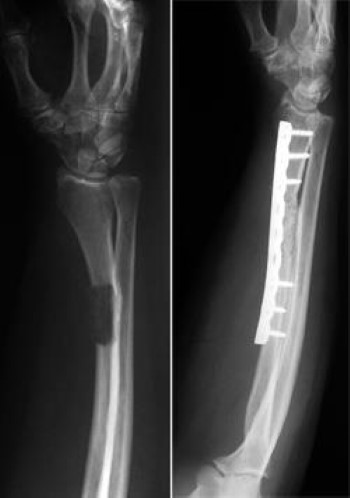

Bone metastases, or osseous metastatic disease, is a category of cancer metastases that results from primary tumor invasion to bone. Those whose bones are affected in the lower part of the body may have difficulty walking. Nevertheless, the optimal approach for metastatic bone disease in rcc has not yet been defined and practical recommendations are rare.

Pelvic bone metastases are a growing concern in the field of orthopedic surgery.

Patients with pelvic metastasis are individually different with different needs of treatment in order to attain the best possible quality of life despite the advanced stage of disease. Metastatic bone disease treatment at herzliya medical center (hmc) is directed through the leadership of professor jacob bickels, who performs unique organ surgery for metastases in the bones by preventing severe functional impairment and the development of disability. A holistic collaboration among the. It's also called metastatic bone disease or secondary bone cancer, because the cancer didn't start in the bones.